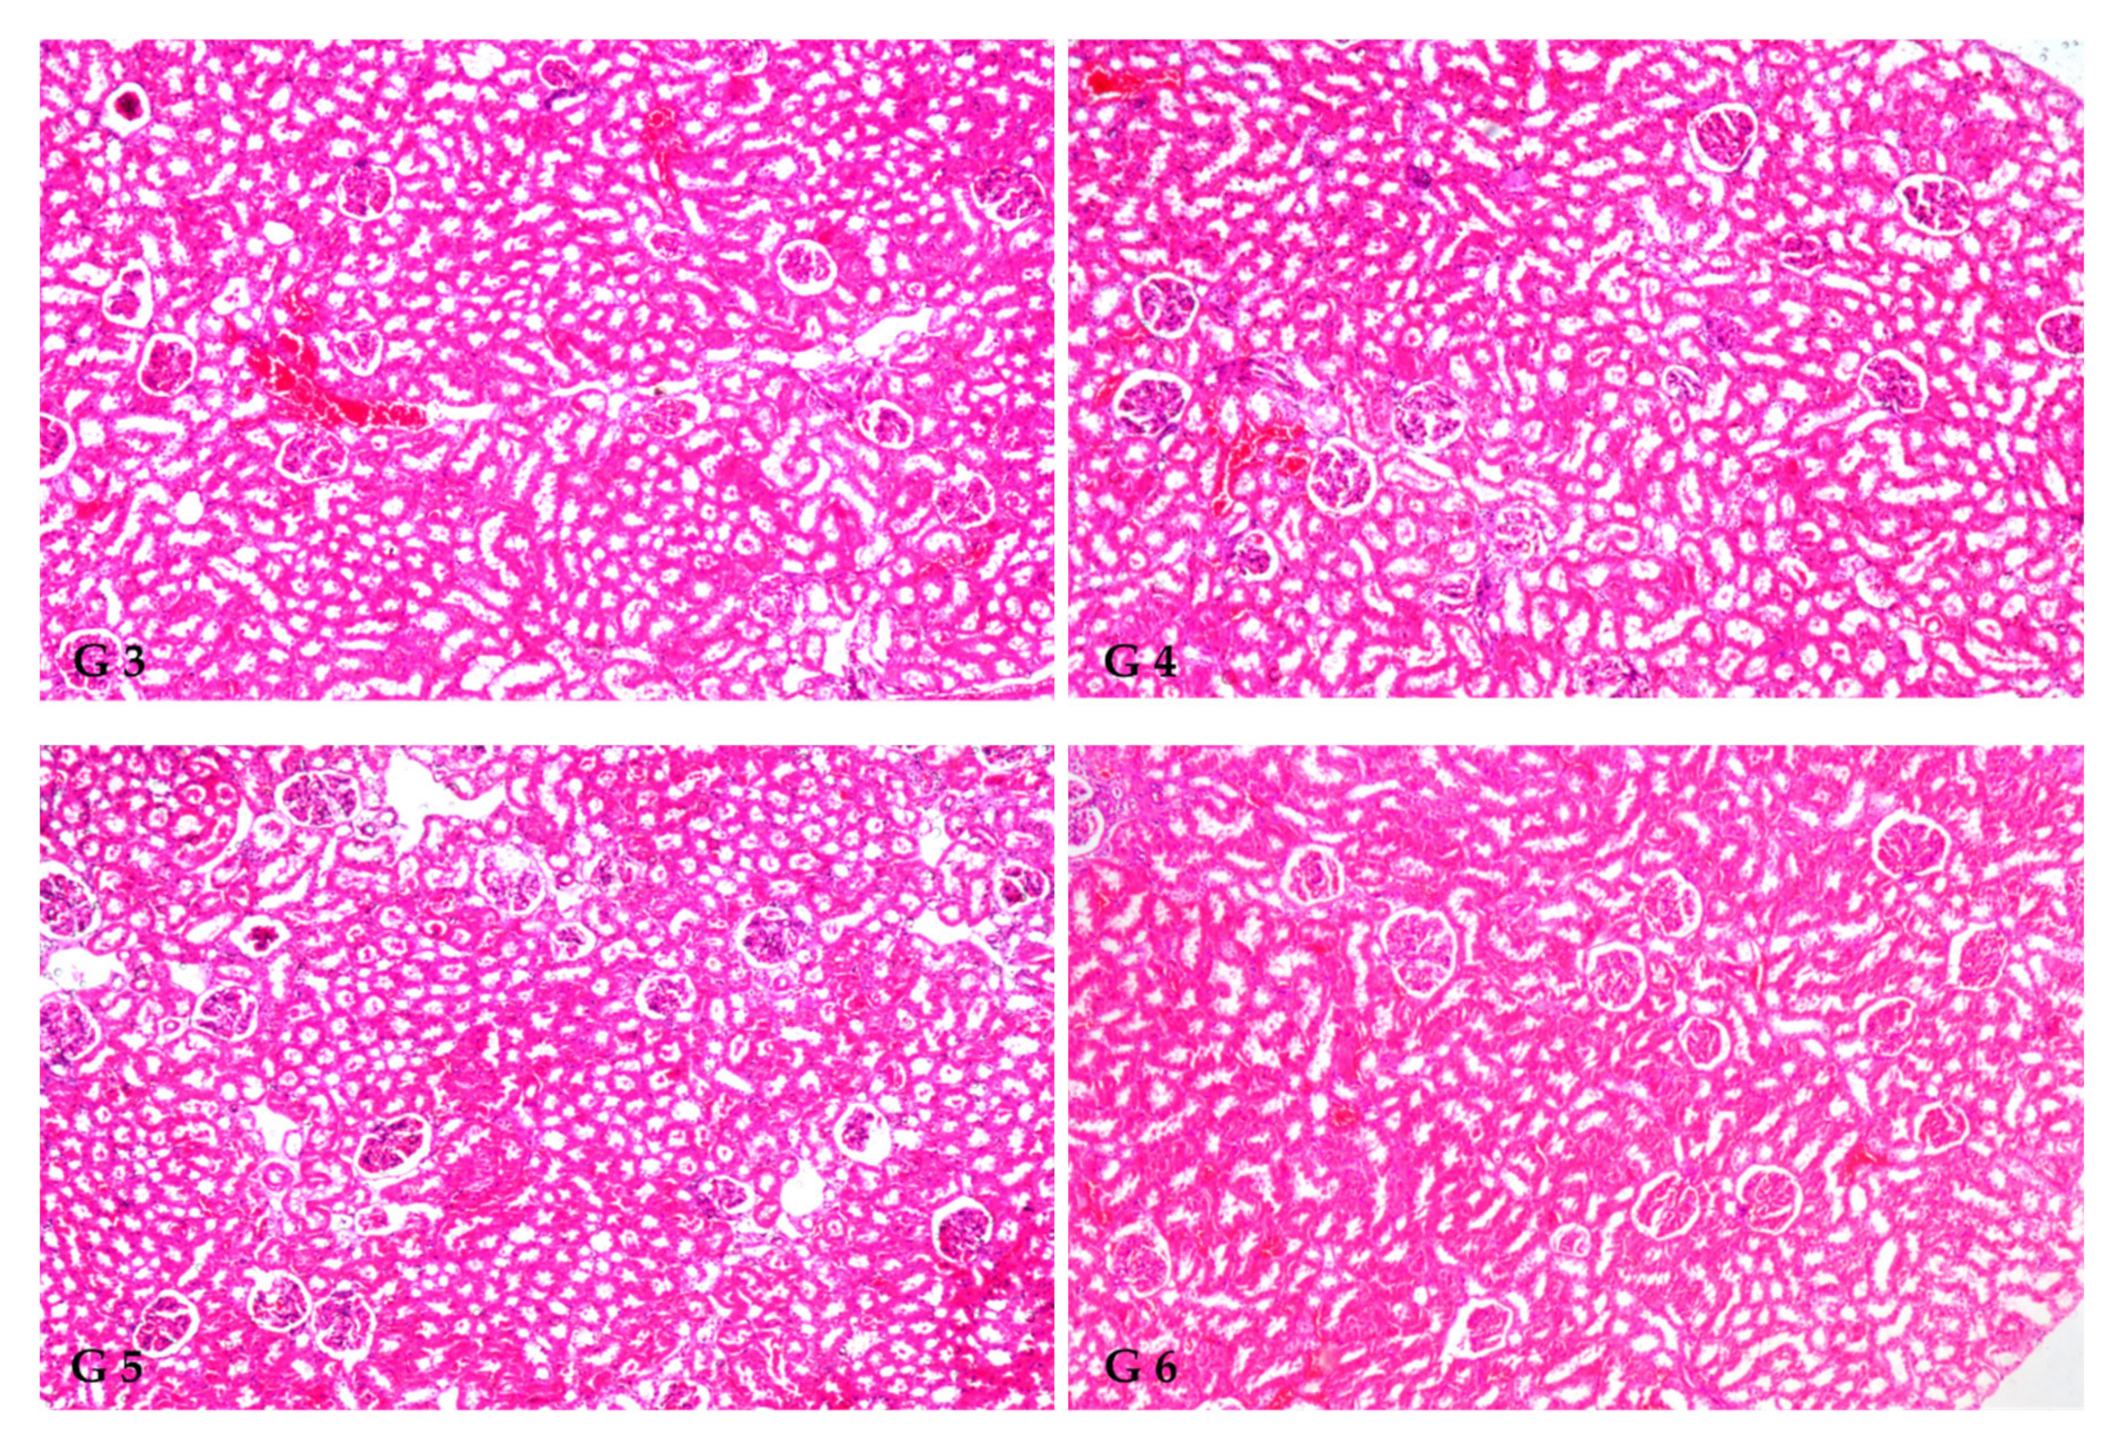

3.8. Renal Histoarchitecture